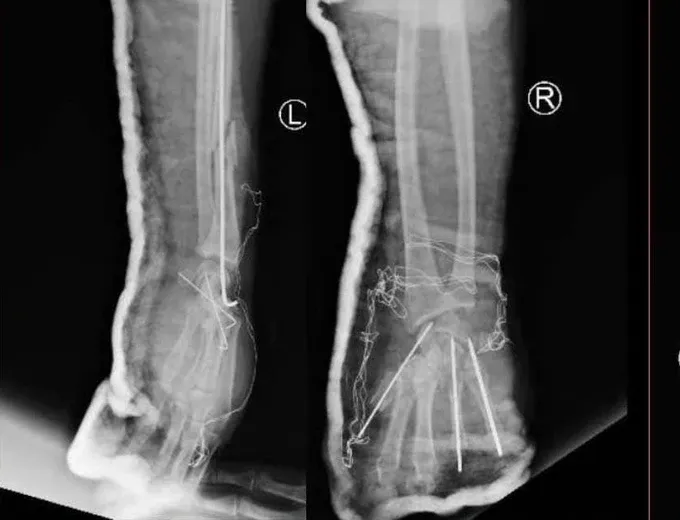

特别是,患者的双手受伤非常严重,右手几乎被炸毁,左手中间有一道纵向裂口,爆炸力导致桡骨骨折。手骨错位,肌腱、肌肉、神经和血管几乎全部从腕管和手掌中脱出。患者立即被医院会诊并转入急诊手术。经过6小时的手术,输了2个单位血液,在麻醉、创伤骨科和综合外科团队的参与抢救下,患者的损伤得到妥善处理。目前,患者情况稳定,继续在创伤骨科进行积极的监测和治疗。

术后的左手和右手的X光片。(图:院方提供)